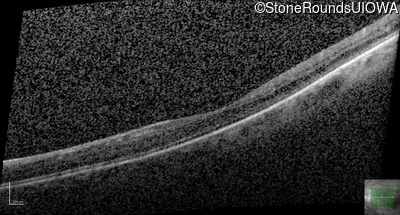

AD Familial Exudative Vitreoretinopathy (IIIE2b)

Age at visit: 32 years